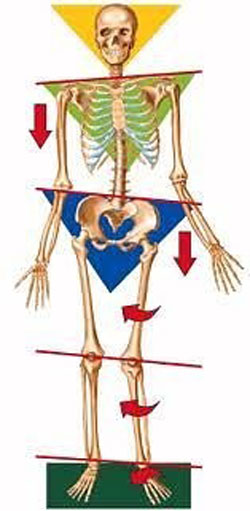

“نابرابری اعضا” به معنای عدم همترازی دو طرفه در طول عضو پایین بدن است و به آن اختلاف طول پاها نیز اطلاق میشود. این وضعیت معمولاً به مشکلاتی در زانوها، لگن، کمر و گردن منجر میشود. این وضعیت از علل متنوعی ناشی میشود. برخی اختلاف طول پاها به صورت دائم و یا “آناتومیک” است و برخی دیگر از آنها قابل برگشت و “عملکردی” هستند.

بسیاری از محققان پزشکی بر این باورند که حتی چند میلیمتر اختلاف طول پاها (یکچهارم اینچ یا حتی کمتر) ممکن است علت اولیه ایجاد درد در قسمت پایین کمر یا ایجاد عوارضی برای رانها شود و فشار زیادی به پاها وارد نماید.

درک این مطلب بسیار مهم است که پاها، زانوها و ستون فقرات همه بخشی از یک ساختار مشابه هستند و اصلاح یکی باعث میشود که بقیه این اجزا در وضعیت بهتری قرار گیرند.

اکثر ما فکر میکنیم که بدن انسان متقارن است؛ اگر یک خط از بالا به پایین میان بدن بکشیم، قسمتهای راست و چپ روی هم منطبق میشوند. در واقع، درجاتی از نامتقارنی نیز در بدن هر فرد وجود دارد. اختلاف طول پا که در آن یک پا آناتومیکی یا عملکردی از پای دیگر کوتاهتر است به عنوان یک “حالت عادی” در نظر گرفته میشوند: عارضهای که بسیار شایع است؛ وجود این حالت تعجبآور نیست.

اختلاف آناتومیکی طول پا به وضعیتی گفته میشود که به دلیل اختلاف در نرخ رشد، شکستگی یا بدشکلی، یک پا از نظر فیزیکی کوتاهتر از پا دیگر است. در اختلاف عملکردی طول پا، هر دو پا طول یکسانی دارند، اما به دلیل عدم تعادل در وضعیت بدن یا انقباض نامتقارن عضلات، یک پا به نظر میرسد که کوتاهتر است. یکی از مثالهایی که میتوان برای اختلاف عملکردی طول پاها ذکر کرد، این است که ساختارهای پای راست (قوس پا، استخوانها، عضلات، تاندونها و غیره) همه به درستی عمل میکنند و طرف راست بدن را در وضعیت استوار نگه میدارند. اما اگر قوس یا استخوانهای پای چپ مشکل داشته باشند، پایداری بدن کاهش مییابد و در نتیجه هنگام ایستادن یا راه رفتن، پا چپ کوتاهتر به نظر میرسد. عملکرد پا چپ در این حالت مانند یک پا کوتاه است زیرا نمیتواند نقش خود را در پایداری بدن به اندازه پا راست ایفا کند. این عدم تعادل ممکن است منجر به اعمال فشار، استرس و درد در زانوها، رانها، لگن و ستون فقرات شود.